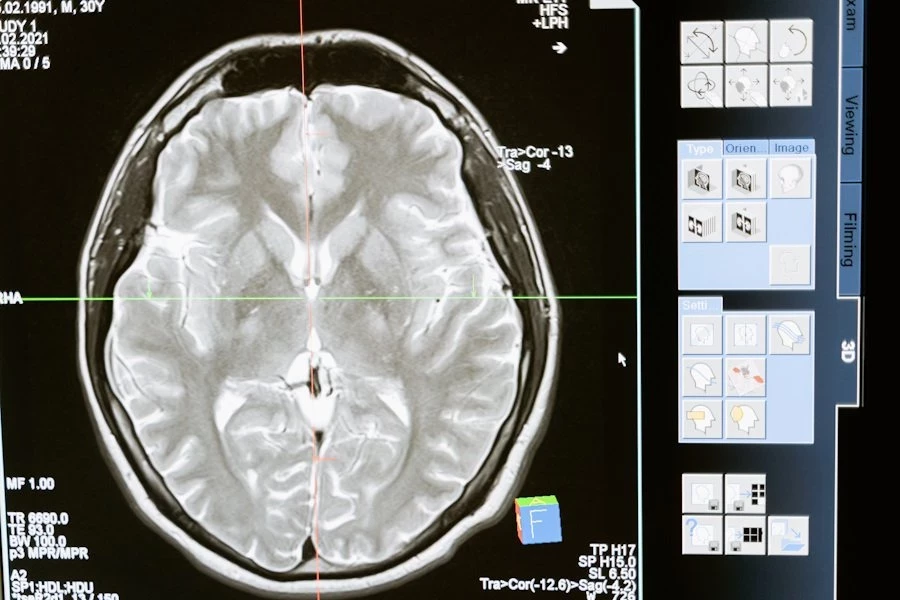

Исследователи утверждают, что эти частицы могут быть управляемы с помощью переменного магнитного поля, что открывает двери для направленной доставки в специфические участки головного мозга и воздействия на его функции.

Согласно обнародованным данным, эта методика предоставляет новые перспективы для лечения нейродегенеративных заболеваний. Предыдущие попытки управления нейронами с применением наночастиц осуществлялись извне, однако в данном исследовании удалось продемонстрировать способность даже простых нанороботов проникать внутрь нейронов, что открывает новые горизонты для медицинской науки.

Эти результаты исследования могут иметь значительное влияние на область медицины. Направленная доставка нанороботов в глубокие участки головного мозга открывает возможности для новых методов лечения нейродегенеративных заболеваний. Также данная технология может использоваться для доставки лекарственных препаратов, включая те, которые направлены на лечение опухолей головного мозга.